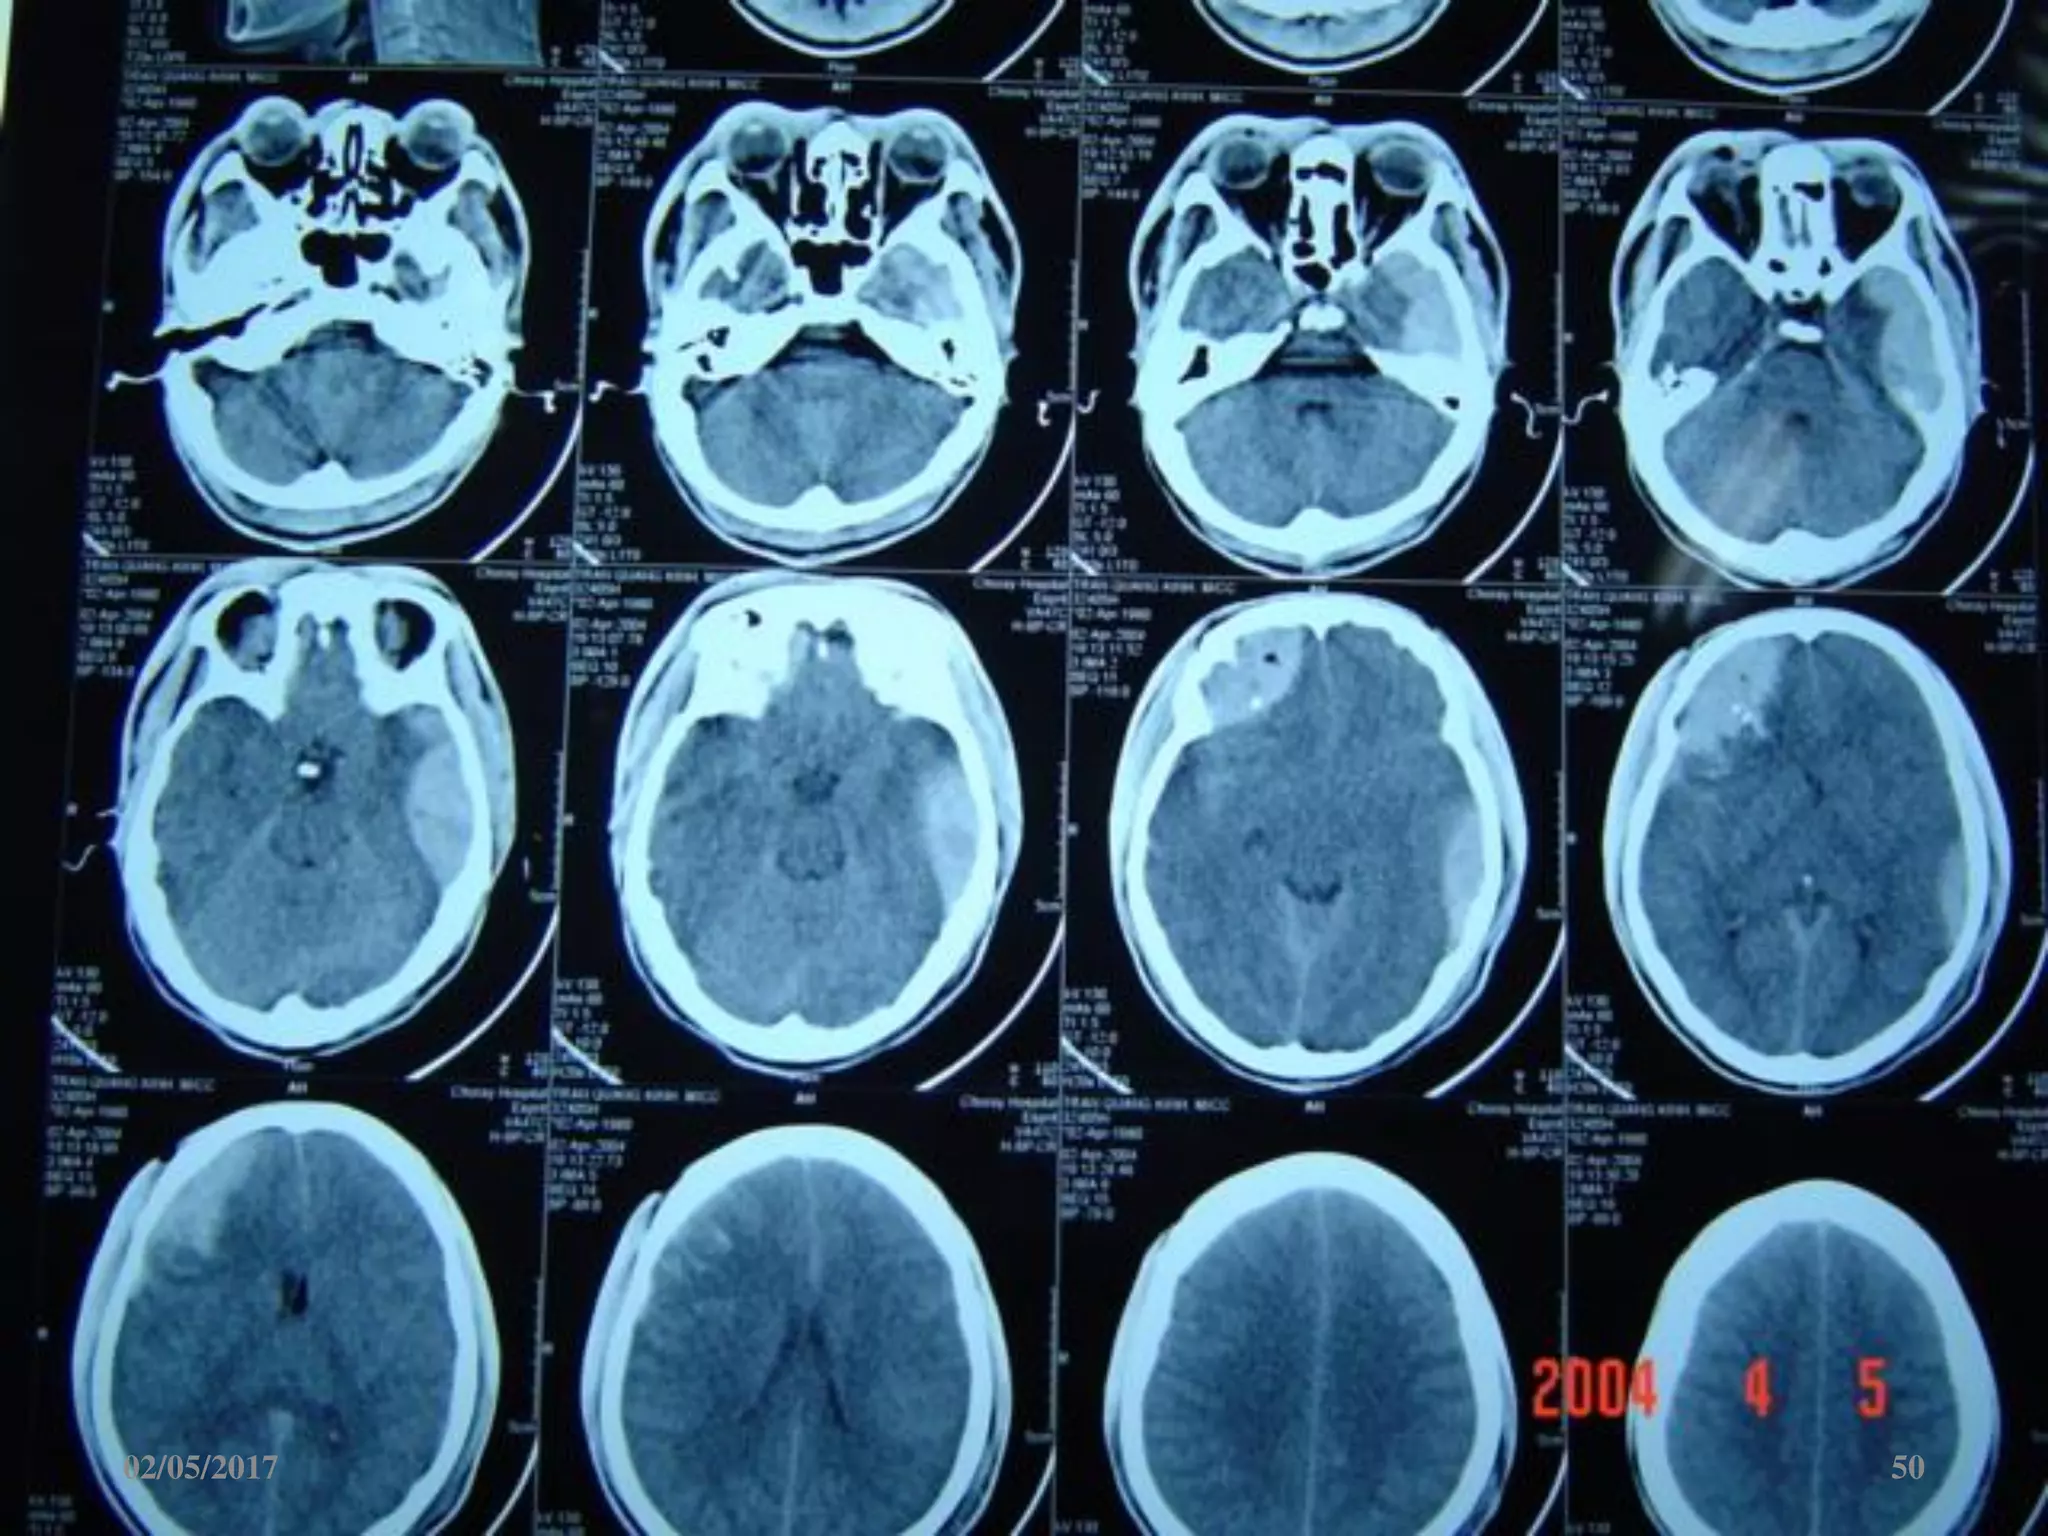

Máu tụ trong não

• Vị trí: trán, thái

dương, đỉnh, chẩm.

• Hình ảnh tăng đậm

độ trong tổ chức não

02/05/2017 60

Máu tụ trongnão • Vị trí: trán, thái dương, đỉnh, chẩm. • Hình ảnh tăng đậm độ trong tổ chức não 02/05/2017 60